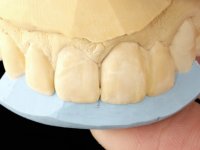

Arcade prints were made with irreversible hydrocolloid, for the lab to prepare an acrylic provisional bridge, with tooth 2.1 as abutment and tooth 2.2 as cantilever pontic. A palatal support was made to be bonded with the palatal surface of tooth 2.3. After removal of the Maryland bridge and the vestibular veneer from tooth 2.1, the dental abutment was re-prepared by making the cervical finish line intrasulcular. The provisional bridge made in the lab was relined on the mouth with self-curing acrylic and composite resin. During 6 weeks the soft tissues were worked and stabilized, preparing the consultation for impression. In this session, gingival separation was performed with kaolin paste, using the provisional bridge to compress the material into the gingival sulcus. Impression was performed using wash technique, and the provisional bridge was placed. At the end of the consultation, an impression was made from the provisional bridge placed in the mouth, using irreversible hydrocolloid. The patient had approved the aesthetics of the provisional. This information was passed on to the lab, where the work followed a silicone index, based on the shape and arrangement of the provisional bridge, approved by the patient. The cantilever bridge was built with a Zr infrastructure, with particular care in designing the connector. After being tried and approved by the patient, the prosthetic was cemented in the mouth with resin modified glass ionomer.